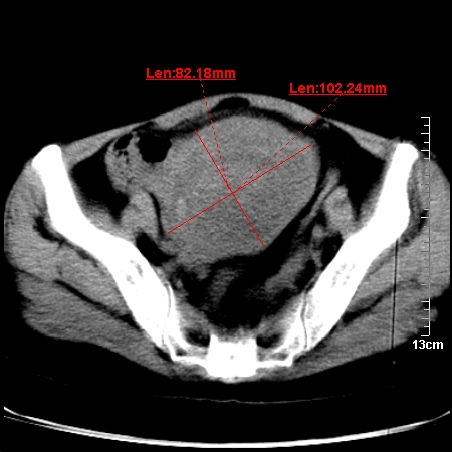

术前的疏忽,手术前诊断阑尾炎,但是没有常规做b超,导致术后1周检查发现 1。实性包块?2。腹腔术后脓肿?

病史:病人一周前诊断阑尾炎,未做b超,手术发现阑尾化脓,(没有留意有无包块),术后1周病人发热,血象:1.6万,做b超发现,随ct检查,上传图片

巨大囊实性包块,边界大部尚清楚,不太像脓肿的表现。应该做个增强检查除外盆腔肿瘤。

脓肿可能性大. 因回盲部区域化脓性兰尾切除残端感染改变征像与实性肿块关系密切.肿块上界至右下腹,下界至盆腔膀胱上缘, 如果是实性肿块在兰尾术中可能就会发现. 所以术后一周病人高烧, 白细胞增高,临床表现支持脓肿.

盆腔一边界大部份清晰囊实性肿块,其周腹脂未见确切异常,其一端与右侧附件相连。考虑右侧附件肿瘤。

如果能进行肠道准备就好了!盆腔内巨大囊实性包块,右前缘与周围肠管分界不清,病灶内前部的气体是否为肠管内气体形成的假象不能确定。

这么大一包快手术当中没有发现?值得怀疑!结合化脓性阑尾炎病史,首先考虑脓肿!不排外附件来源的肿瘤,建议增强扫描!!